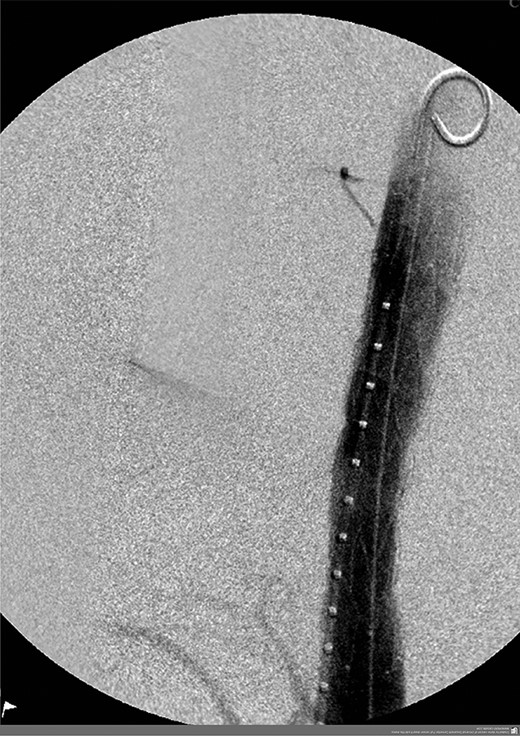

A 57-year-old male presented haemodynamically unstable with a blood pressure of 85/50 mmHg and a heart rate of 136 bpm with haematemesis, melaena and 4-day history of back pain. Fifteen years previously he was treated for a poorly differentiated adenocarcinoma (pT3 pN1 MX) close to the gastro-oesophageal junction with chemotherapy and trans-hiatal oesophagectomy. He received no radiotherapy. Apart from being a life-long smoker he had no other positive social risk factors or medical history. He underwent immediate oesophago-gastro-duodenoscopy (OGD). This showed fresh and clotted blood in the gastric remnant but no bleeding source was identified. He had a pulseless arrest during the OGD but underwent successful cardiopulmonary resuscitation. Following this a CT angiogram was performed. This demonstrated a fistula between the neo-oesphagus and the thoracic aorta (Fig. 1). Following discussion between an upper gastro-intestinal surgeon, a vascular surgeon and an interventional radiologist the patient was taken to the operating theatre. Under general anaesthesia an initial thoracic aortogram was performed from the right groin to confirm the presence and location of the AGF (Fig. 2). Following this, a covered thoracic stent graft (Cook Medical ZTA-24-105/diameter of 24 mm and length of 105 mm), was inserted via the femoral artery under image guidance. The stent graft, usually used in aneurysmal repair, was placed in the thoracic aorta across the fistula and occluded it. Subsequent angiogram showed no leak (Fig. 3). The patient became haemodynamically stable and had an uneventful recovery.

Angiogram prior to primary aortic stenting; leak via fistula demonstrated by arrow.